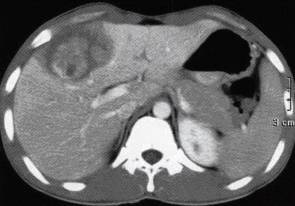

图1肝炎性肌纤维母细胞瘤

A.肝左叶内侧段不均匀低密度,边缘模糊;

B.增强扫描动脉期病灶内强化核团略低于肝实质密度;

C.门脉期病灶中心核团状强化,程度稍低于肝脏密度,周围伴有低密度不强化环带;

D.延迟10分钟扫描病灶边缘及间隔强化呈略低于肝脏密度,病灶内低密度环消失